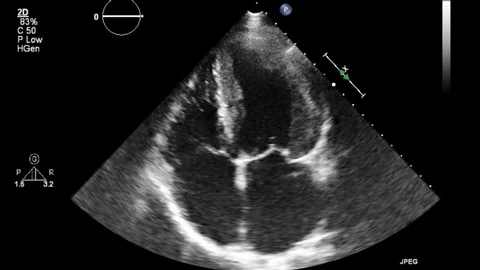

Our platform provides access to a rich and diverse collection of medical datasets designed to support research, innovation, and advanced analytics in healthcare. These datasets span multiple clinical domains and imaging modalities, enabling comprehensive analysis and model development.